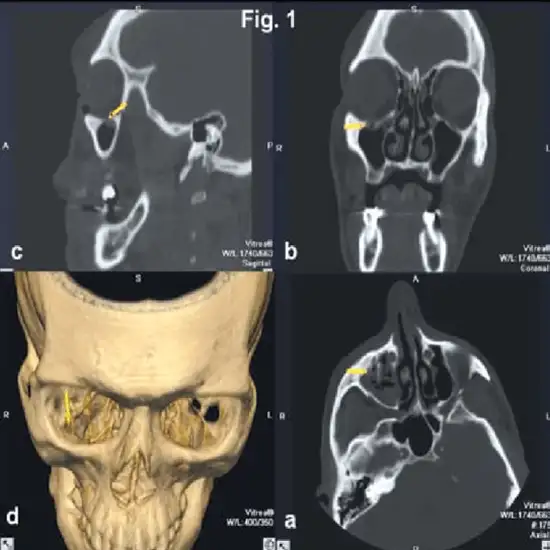

3D CT Orbit is a 3D reconstruction imaging scan used to visualise the bony structure of the orbit and pathology conditions.

It is an imaging method is a computed tomography (CT) scan of the orbit. It makes detailed images of the eye sockets (orbits), eyes, and surrounding bones using x-rays.

Slices are separate images of the body created by a computer. These images can be saved, viewed on a computer monitor, or printed on film. By stacking the slices together, the computer can create three-dimensional models of the body area.

An orbit CT scan can also be used to detect the following:

• Broken eye socket bone

•  Foreign object in the eye socket